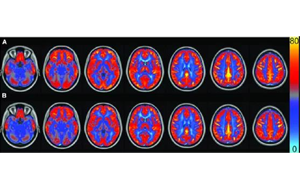

顱腦創(chuàng)傷后的繼發(fā)性腦損傷是怎么發(fā)生的?Science:補(bǔ)體介導(dǎo)炎癥及神經(jīng)損傷!

創(chuàng)傷性腦損傷 (TBI)是導(dǎo)致兒童和成人殘疾的主要原因之一。每年,TBI 影響著全球6900余萬人,可能導(dǎo)致認(rèn)知功能障礙、感覺處理困難、睡眠中斷和癲癇等不良后果。其中大多數(shù)在TBI發(fā)生后數(shù)月或數(shù)年由繼發(fā)性損傷引起。TBI的原發(fā)損傷本質(zhì)上是不可逆轉(zhuǎn)的,因此,了解繼發(fā)性損傷發(fā)生的時(shí)間、節(jié)點(diǎn)和機(jī)制對(duì)于預(yù)防或治療TBI后殘疾至關(guān)重要。